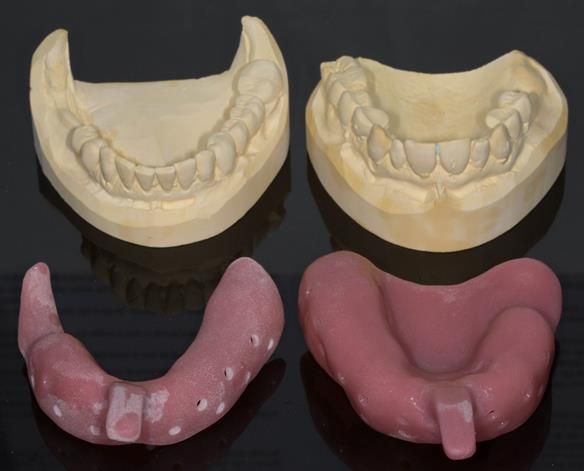

This newsletter describes in step by step detail Angela's transition through immediate partial dentures to crown supported definitive metal based dentures.

The clinical situation and treatment process is shown in detail below with photographs. I (Finlay Sutton) provided the clinical work and Rowan Garstang provided the technical work.